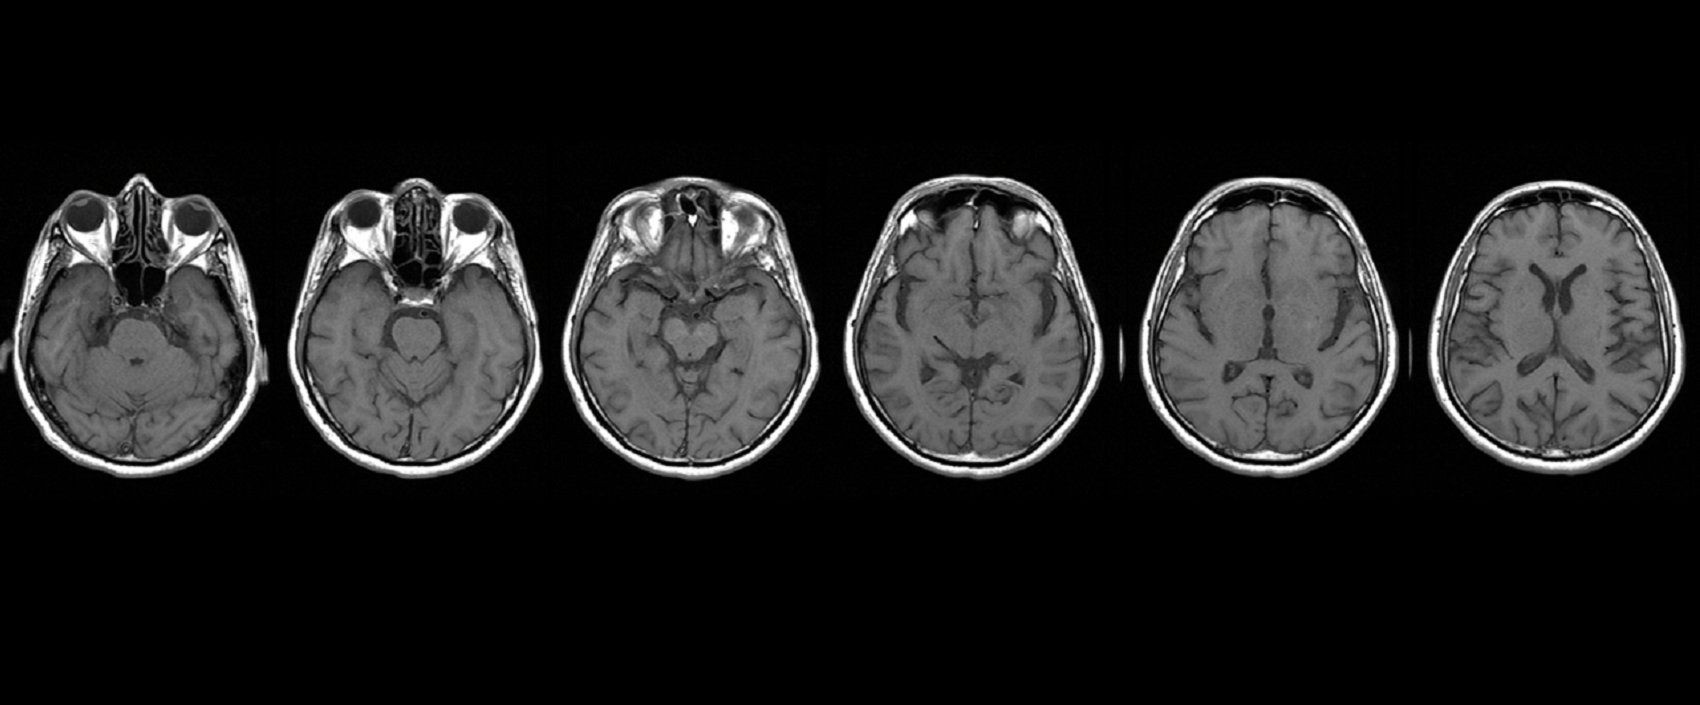

Pesquisadores israelenses desenvolveram uma ferramenta de imagem para diferenciar casos de tumor cerebral que, após o tratamento, estão de fato...

Num quadro de doença neurológica, quanto maior for o dano cerebral sofrido, maior será o impacto sobre a cognição do...